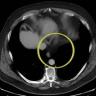

The authors present a clinical video highlighting the technique used to perform a completely minimally invasive Ivor Lewis esophagectomy for a patient with a history of open Nissen fundoplication performed as an infant for GERD who developed esophageal adenocarcinoma as an adult.

Minimally Invasive Esophagectomy After Pediatric Nissen Fundoplication for Esophageal Adenocarcinoma